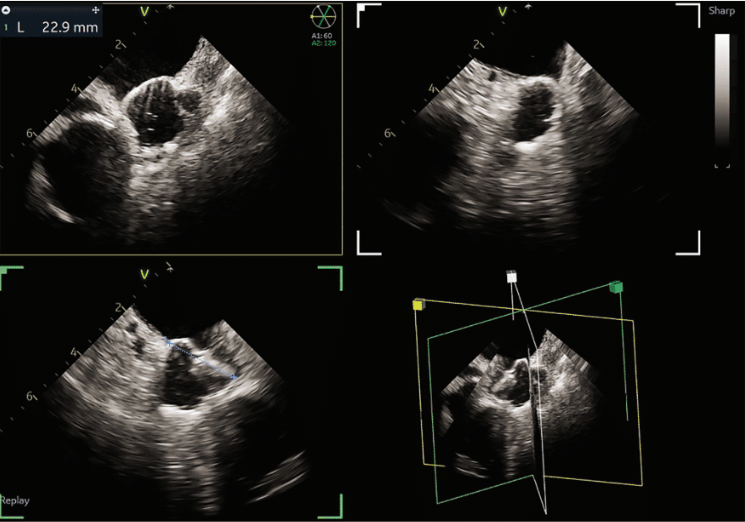

quickly adopted for most cases. The typical workflow for incorporating the 4D ICE catheter involves femoral venous access in the usual manner. To begin a case, the catheter is inserted into the right atrium (RA) and screened for pericardial effusion. Using the V-Plane feature, the LV pericardium can be visualized as well. The catheter is then deflected across the tricuspid valve and into the right ventricular outflow tract. V-Plane through the appendage, in addition to standard 2D imaging, can exclude LAA thrombus (Figure 1). The catheter is withdrawn back to the RA and imaging of the interatrial septum is obtained to help guide transseptal puncture in the usual manner. Once puncture is completed, the septum is flossed with the transseptal sheath. The sheath is then pulled back to the inferior vena cava (IVC). The ICE catheter is then withdrawn to the low RA with direct visualization of the wire as it crosses the septum. Under ultrasound and fluoroscopic guidance, the ICE catheter is pushed across the septum into the mid LA. The delivery sheath is then pushed across the puncture site into the LA. The ICE catheter can be positioned in different locations throughout the LA; however, placement along the mitral annulus frequently allows adequate visualization of the LAA (Figure 2). Multiplanar imaging of the LAA allows for device sizing and selection (Figure 3). Once a device size is selected, the implant is prepped and delivered using multiplanar and fluoroscopic imaging. During sheath manipulation and device delivery, the sonographer can make fine adjustments to the image to maintain adequate visualization so the operator can focus on device delivery. Once an implant is delivered, confirmation of position and occlusion can easily be performed by color flow Doppler and 2D/3D imaging (Figure 4). At the end of the procedure, a quick survey can exclude pericardial effusion.